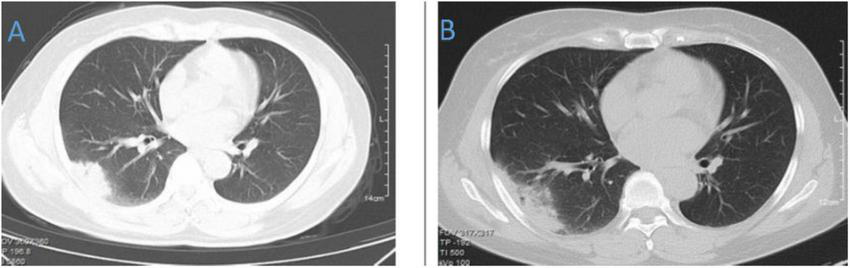

FIGURE 4

Chest CT of patient 4. (A) Before treatment on 2021.10.26. (B) The follow-up imaging at 1 week post-treatment showed stable findings compared to the pre-treatment scans.

FIGURE 5

Chest CT of patient 5. (A) Before treatment on 2021.10.19. (B) The follow-up imaging at 1 week post-treatment showed stable findings compared to the pre-treatment scans.

FIGURE 6

Chest CT of patient 6. (A) Before treatment on 2021.10.19. (B) The follow-up imaging 1 week after treatment showed progression compared to the pre-treatment scans.